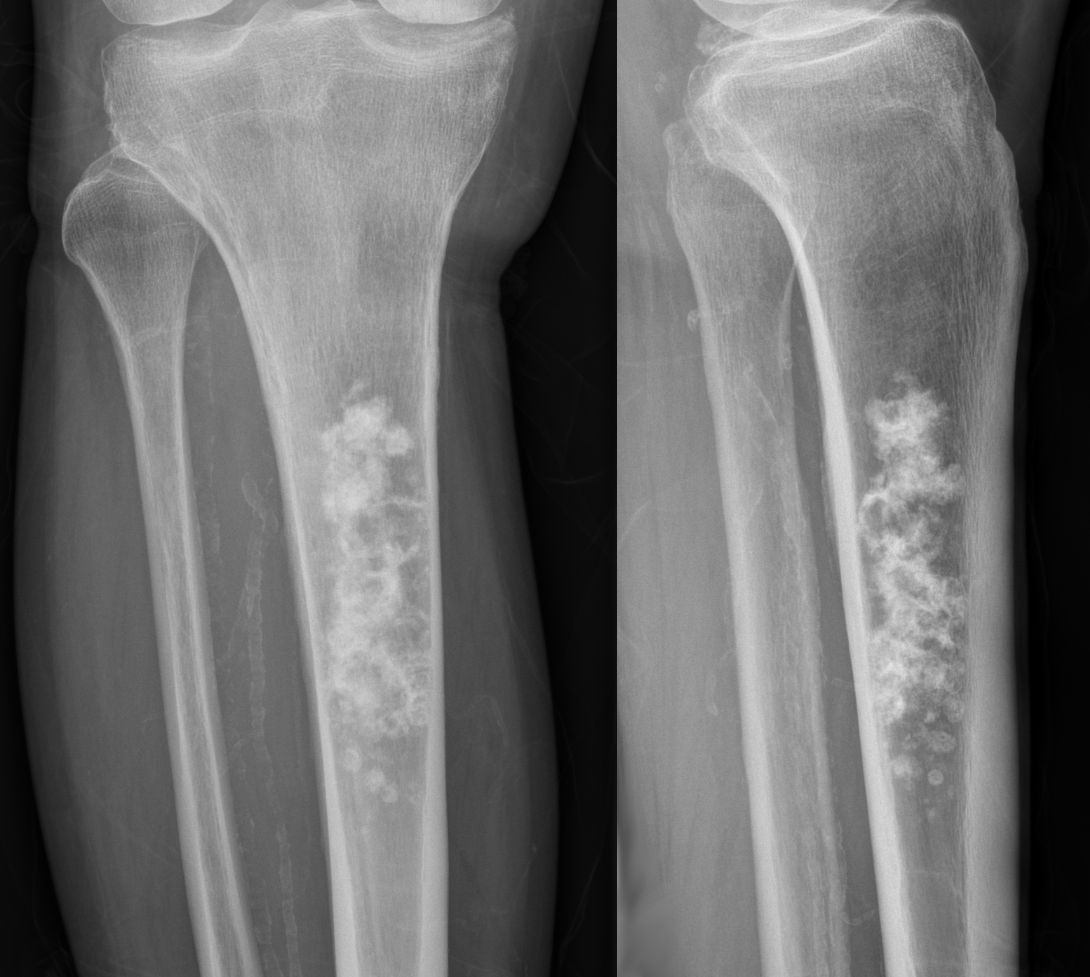

Рентгеновские снимки саркомы плечевого сустава